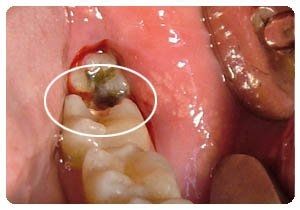

龋齿的表现以色、形、质的改变为主,其中以质变为主,色、形变化是质变的结果,随着病程的发展,病变由釉进入牙本质,组织不断被破坏、崩解而逐渐形成龋洞,临床上常根据龋坏程度分为浅、中、深龋三个阶段。>>点击在线咨询详情<<

深龋:龋坏已达牙本质深层,一般表现为大而深的龋洞,或入口小而深层有较为广泛的破坏,对外界刺激反应较中龋为重,但刺激源去除后,仍可立即止痛,无自发性痛。>>点击在线咨询详情<<